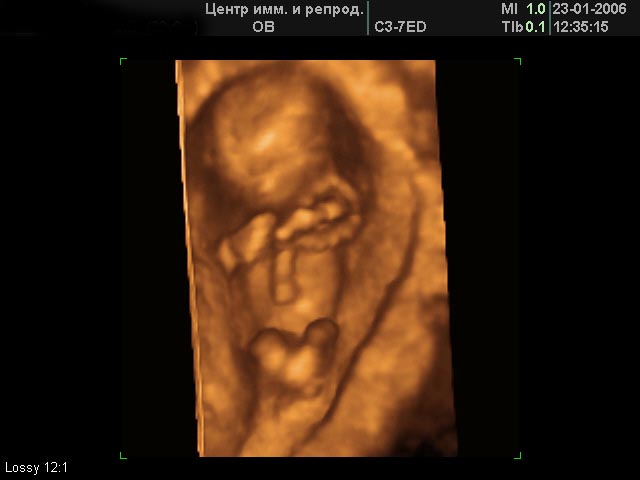

Лицо 23-24 недели

Лицо 26-27 недель

Лицо 27-28 недель

Лицо 30-31 неделя

Лицо 31-32 недели

Лицо 33-34 недели

Лицо 34-35 недели